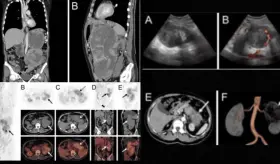

Las infecciones de las vías urinarias aumentan progresivamente en los pacientes masculinos después de los 50 años y a menudo se asocian con epididimitis, orquitis, prostatitis, pielonefritis, uretritis y catéteres urinarios infectados y suelen estar relacionadas con anomalías anatómicas, pero pueden asociarse a otros muchos factores de riesgo.